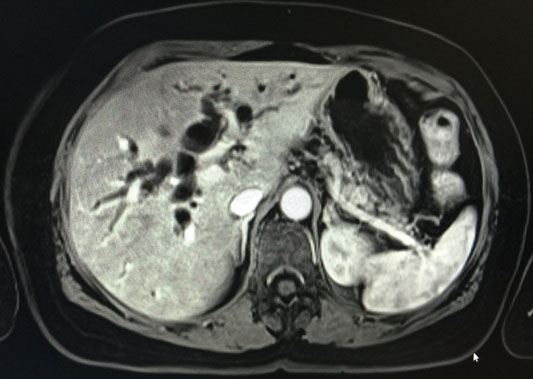

A magnetic resonance imaging (MRI) with magnetic resonance cholangiopancreatography (MRCP) revealed intra and extrahepatic biliary and pancreatic ductal dilatation, with gallbladder hydrops secondary to an obstructing lesion involving the distal CBD and pancreatic duct. The CBD was 1.7 cm with no obstructing calculus. There was a poorly defined heterogeneously enhancing soft tissue mass involving pancreatic head and uncinate process measuring 3.5 × 3.5 × 2.0 cm, which encases and obstructs the distal CBD and pancreatic duct, and abuts the duodenal wall at D2–D3 segment. Few nonspecific subcentimeter peripancreatic, aortocaval, and para-aortic lymph nodes, measuring up to 7 mm in short axis diameter, were seen (Figure 1 and Figure 2).

Figure 1: MRI showing intra/extrahepatic biliary and pancreatic ductal dilatation.